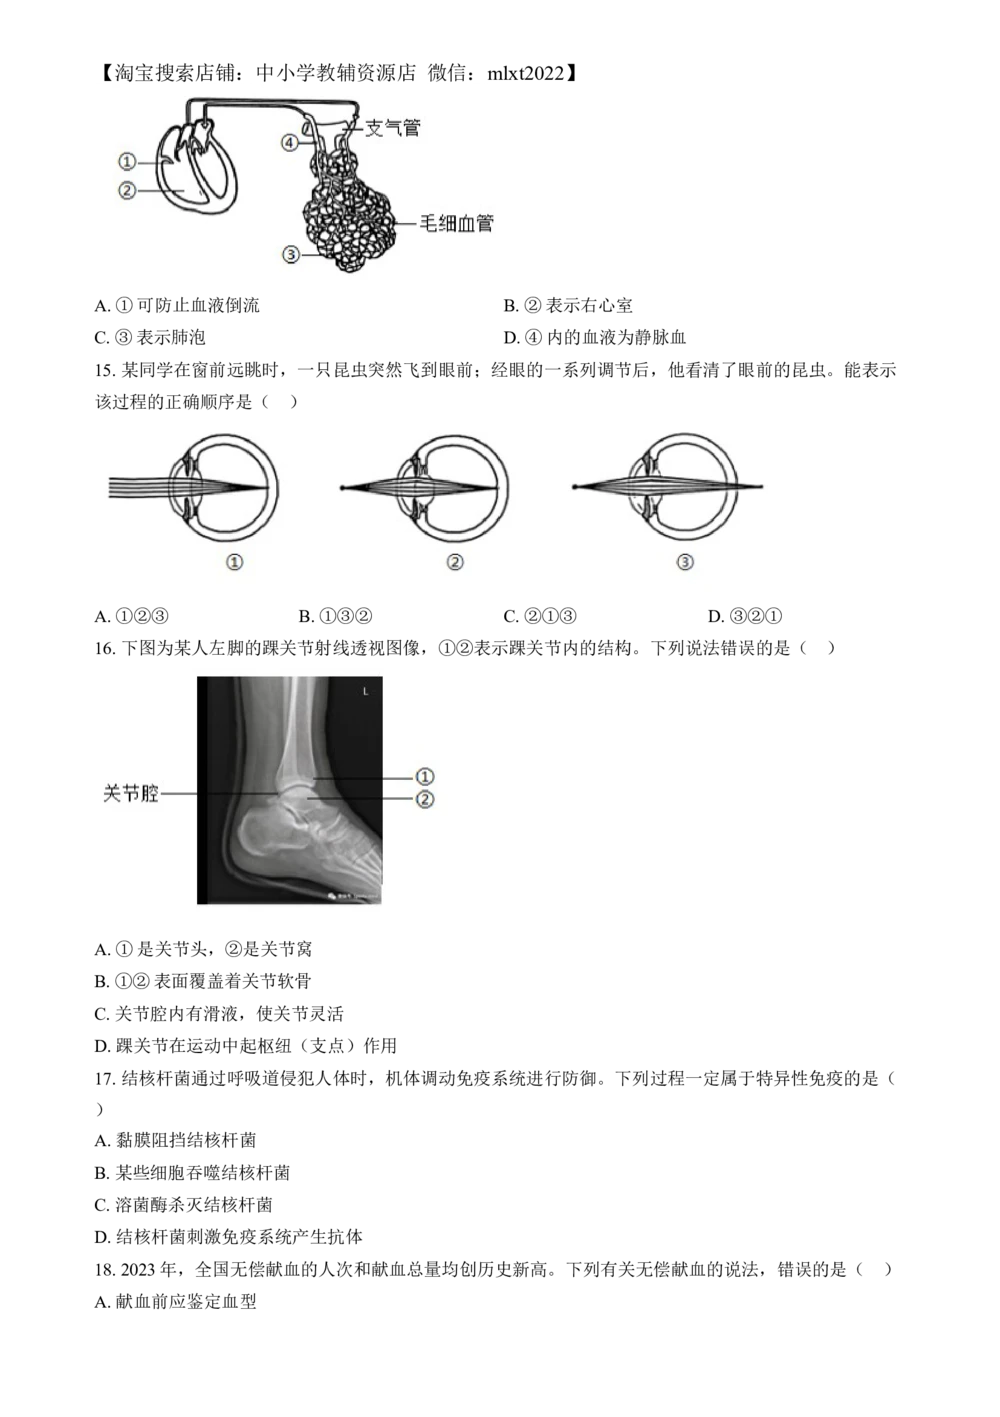

【淘宝搜索店铺:中小学教辅资源店 微信:mlxt2022】 机密★启用前 2024 年河北省初中学业水平考试(八年级) 生物学试卷 注意事项:1.本试卷共8页,总分60分,考试时间60分钟。 2.答题前,考生务必将姓名、准考证号填写在试卷和答题卡的相应位置。 3、所有答案均在答题卡上作答,在本试卷或草稿纸上作答无效。答题前,请仔细阅读答题 卡上的“注意事项”,按照“注意事项”的规定答题。 4.答选择题时,用2B铅笔将答题卡上对应题目的答案标号涂黑;答非选择题时,请在答题 卡上对应题目的答题区域内答题。 5.考试结束时,请将本试卷和答题卡一并交回。 一、选择题(本大题共25小题,每小题1分,共25分。在每小题给出的四个选项中,只有 一项最符合题意) 1. 细胞是生命起源的标志和生物进化的起点。所有细胞均具有的结构是( ) A. 细胞壁 B. 成形的细胞核 C. 叶绿体 D. 细胞膜 2. 下列有关细胞分裂和细胞分化的说法,错误的是( ) A. 一个草履虫通过细胞分化形成两个草履虫 B. 幼苗生长时,细胞分裂和细胞分化旺盛 C. 受精卵形成新个体离不开细胞分裂和细胞分化 D. 此时我们身体内有些细胞正在进行分裂或分化 3. 河北武强木版年画是国家级非物质文化遗产。下列年画作品表示的四种动物中,体温不恒定的是( ) A. 牛 B. 虎 C. 蛇 D. 鸡 4. 下图为天竺葵叶及其内部结构示意图。图中没有包含的植物体结构层次是( ) A. 细胞 B. 组织 C. 器官 D. 个体 5. 用我们所学生物学知识分析,下列说法错误 是( ) A. 煤主要是由古代蕨类植物的遗体形成的【淘宝搜索店铺:中小学教辅资源店 微信:mlxt2022】 B. 葫芦藓有根、茎、叶的分化,适于陆地生活 C. 种子植物的繁殖过程摆脱了对水环境的依赖 D. 青藏铁路设置的野生动物通道,减少了对藏羚迁徙的干扰 6. 萝卜、白菜是常见的蔬菜,这两种植物在生物学上的分类地位如下图所示。图中包含植物种类最多的分 类等级是( ) A. 植物界 B. 白花菜目 C. 十字花科 D. 萝卜属 7. 2023年,河北省对72个县域开展生物多样性调查,发现了水杉、银杉、白鹈鹕、黑嘴鸥、细鳞鲑、松 江鲈等60余种国家重点保护动植物,丰富了我省野生动植物资源数据库。下列不属于野生动植物资源保 护措施的是( ) A. 就地保护 B. 国家颁布实施相关法律法规 C. 异地保护 D 完全禁止利用 8. 同学们在路边发现了一种生长异常茂盛的植物。查阅资料获知,该植物中文名为喜旱莲(如下图所 示),属于外来入侵植物。下列做法错误的是( ) A. 将喜旱莲子草移栽到校园 B. 向有关部门报告喜旱莲子草的情况 C. 积极参与清除喜旱莲子草的行动 D. 向周围人群宣讲外来物种入侵的危害 9. 馒头是中国传统发酵食品。制作馒头用到的微生物主要是( ) A. 青霉 B. 噬菌体 C. 酵母菌 D. 醋酸菌 10. 某同学早晨冲了一杯浓香的黑芝麻糊,其主要原料是黑芝麻种子。黑芝麻种子的营养物质主要贮存在【淘宝搜索店铺:中小学教辅资源店 微信:mlxt2022】 ( ) A. 胚芽 B. 胚根 C. 胚轴 D. 子叶 11. 野生大豆(如下图所示)在我国分布广,种类多。从野生大豆中筛选出的高蛋白、低脂肪等优质基 因,可转入普通大豆体内培育新品种。下列关于野生大豆的说法,错误的是( ) A. 属于被子植物 B. 根瘤中的根瘤菌能固氮 C. 豆荚由花中的胚珠发育而来 D. 是大豆育种的基因资源库 12. 为研究施肥深度对干旱条件下小麦光合作用的影响,研究人员在相同条件下,选择符合实验标准的三 个地块施肥、播种,长出植株后进行检测,实验数据(单位已省略)如下表所示。下列说法错误的是( ) 实验处理 浅施(15cm) 中施(30cm) 深施(45cm) 生理指标 叶绿素含量 1.8 2.1 2.5 气孔导度 0.12 0.15 0.18 光合作用速率 18.5 22.3 26.7 注:气孔导度数值越大,表示气孔开放程度越大。 A. 本实验控制的变量是施肥深度 B. 随着施肥深度增加,小麦蒸腾作用减弱 C. 小麦的光合作用速率与气孔开放程度、叶绿素含量有关 D. 干旱条件下深施肥提高了小麦的光合作用速率 13. “曲曲折折的荷塘上面,弥望的是田田的叶子”描写了池塘中荷叶相连的景色,下列能直接发育成荷 叶的是( ) A. 花芽 B. 芽轴 C. 幼叶 D. 芽原基 14. 下图为肺循环示意图,箭头表示血流方向,①②③④表示结构。下列说法错误的是( )【淘宝搜索店铺:中小学教辅资源店 微信:mlxt2022】 A. ①可防止血液倒流 B. ②表示右心室 C. ③表示肺泡 D. ④内的血液为静脉血 15. 某同学在窗前远眺时,一只昆虫突然飞到眼前;经眼的一系列调节后,他看清了眼前的昆虫。能表示 该过程的正确顺序是( ) A. ①②③ B. ①③② C. ②①③ D. ③②① 16. 下图为某人左脚的踝关节射线透视图像,①②表示踝关节内的结构。下列说法错误的是( ) A. ①是关节头,②是关节窝 B. ①②表面覆盖着关节软骨 C. 关节腔内有滑液,使关节灵活 D. 踝关节在运动中起枢纽(支点)作用 17. 结核杆菌通过呼吸道侵犯人体时,机体调动免疫系统进行防御。下列过程一定属于特异性免疫的是( ) A. 黏膜阻挡结核杆菌 B. 某些细胞吞噬结核杆菌 C. 溶菌酶杀灭结核杆菌 D. 结核杆菌刺激免疫系统产生抗体 18. 2023年,全国无偿献血的人次和献血总量均创历史新高。下列有关无偿献血的说法,错误的是( ) A. 献血前应鉴定血型【淘宝搜索店铺:中小学教辅资源店 微信:mlxt2022】 B. 献血时从手臂动脉取血 C. 献血后应适当多摄入蛋、奶等食物 D. 献血后体内血液成分短期内可恢复正常 19. 飘飞的杨絮来自杨的雌株。用杨的雄株枝条扦插繁育新植株,逐渐替换雌株,是解决杨絮飘飞的一种 方法。下列实例中,与杨的扦插不属于同一种生殖方式的是( ) A. 玉米杂交育种 B. 人参组织培养 C. 桃的嫁接 D. 体细胞克隆牛 20. 同学们用3D打印技术制作了表示细胞核、染色体、DNA和基因关系 模型,如下图所示。其中a表 示的是( ) A. 细胞核 B. 染色体 C. DNA D. 基因 21. 某人出现食量大、消瘦、心跳快、情绪易激动等症状。经化验,发现他的体内某种激素水平偏高,医 生诊断其患甲亢。该激素是( ) A. 胰岛素 B. 性激素 C. 甲状腺激素 D. 生长激素 22. 狗由古代狼经长期驯化而来。科研人员对比狗和狼的面部肌肉,发现大多数狗的眼周围多了两块肌 肉,如下图所示。这两块肌肉相互配合使狗能表现出“可怜巴巴”的表情,但哈士奇(狗的品种)没有旁 侧眼睑牵拉肌。下列说法错误的是( ) A. 推测有的古代狼眼周围有这两块肌肉 B. 控制这两块肌肉的基因可遗传给后代 C. 狗“可怜巴巴”的表情是自然选择的结果 D. 哈士奇与其他品种狗的表情可能不同 23. 我们吃的食物进入消化道会发生各种变化。下列说法错误的是( ) A. 部分淀粉在口腔内分解为麦芽糖 B. 蛋白质在胃内全部分解为氨基酸【淘宝搜索店铺:中小学教辅资源店 微信:mlxt2022】 C. 脂肪经胆汁作用形成脂肪微滴 D. 脂肪在小肠内分解 甘油和脂肪酸 24. 蝇子草有雌株和雄株之分,其性别决定方式与人类相同。蝇子草体细胞中含有22条常染色体和2条性 染色体。正常情况下,蝇子草卵细胞中染色体组成是( ) A. 11条常染色体+X染色体 B. 11条常染色体+Y染色体 C. 22条常染色体+X染色体 D. 22条常染色体+Y染色体 25. 2022年,在河北围场早白垩纪地层中发现了完整的古七鳃鳗化石(如下图所示)。对该化石研究得 知,古七鳃鳗具有鳃孔、背鳍和尾鳍等结构特征,与现存的七鳃鳗相似。下列说法错误的是( ) A. 围场在早白垩纪时期有古七鳃鳗分布 B. 古七鳃鳗具有鳃孔和鳍,适于陆地生活 C. 现存的七鳃鳗可能由古七鳃鳗进化而来 D. 古七鳃鳗化石是研究七鳃鳗进化的直接证据 二、非选择题(本大题共5小题,共35分) 26. 河北是全国第一产梨大省。某生物小组到产梨基地开展研学活动,发现果农为提高梨的产量和品质采 取了多种措施。回答下列问题. (1)果农定期施用有机肥料。土壤中的微生物将有机肥料中的有机物分解成二氧化碳、水和______等, 其中二氧化碳可被梨树叶片吸收,用于________(填“光合作用”或“呼吸作用”)。 (2)果农适时对梨树进行环剥,环剥是将树干上的一圈树皮剥去。此处理可暂时阻断叶片制造的 ________沿茎中的______向下运输,使其更多地留在环剥口上方,从而促进花芽的发育。 (3)果农通常采用人工授粉的方法提高梨树的坐果率。人工授粉时,可将两朵花面对面轻轻转动摩擦, 确保花粉粘到雌蕊的______上。 (4)夏秋时节是梨果实发育和成熟的关键期。这段时间,产梨基地日照时间可长达12小时,昼夜温差在 10℃以上,有利于提高梨的产量,原因是________。 27. 发展生态农业,助力乡村振兴。某地积极开发低洼盐碱地渔农综合利用模式,如下图所示。【淘宝搜索店铺:中小学教辅资源店 微信:mlxt2022】 回答下列问题。 (1)低洼盐碱地种植的紫花苜蓿不仅长势良好,而且能降低土壤盐碱度,增加土壤肥力。这说明它既能 适应环境,也能______环境。 (2)台田上的小麦和紫花苜蓿,属于该生态系统组成成分中的________。它们固定的太阳光能,通过 ______在生物之间传递。 (3)池塘中,鲢鱼主要以浮游植物为食,生活在水体上层;鳙鱼主要以浮游动物为食,生活在水体上层 或中上层。鲢鱼和鳙鱼的种间关系是________。养殖时发现,鲢鱼和鳙鱼的配比为3:7时,池塘生态系 统保持平衡;鲢鱼和鳙鱼的配比为1:1时,水质受污染程度较高,池塘生态系统失去平衡。这说明生态 系统的________有一定限度。 (4)此模式使种植和养殖有机结合,实现了对该生态系统________和能量的充分利用。加工厂对农副产 品进行深加工,满足了________的生活需求,提升了低洼盐碱地的生态效益和经济效益。 28. 某人因侧腹部疼痛就医,遵医嘱憋尿进行超声检查,发现肾脏中有结石。下图为人体泌尿系统组成及 部分内部结构纵切示意图,①②③表示结构。 回答下列问题。 (1)健康人的血液由肾动脉流入肾脏后,通过肾小球和肾小囊的________作用形成原尿。原尿中大部分 水、全部________和部分无机盐等被肾小管重新吸收,随血液通过肾静脉汇入________,流回心脏的右心 房;剩下的物质形成尿液。 (2)当膀胱中的尿液储存到一定量时,位于膀胱壁内的________受到刺激后产生神经冲动,“装满尿 液”的信息沿______传到脊髓中的排尿中枢,同时上传到大脑皮层,产生尿意;需要憋尿时,大脑下 达“指令”,尿道括约肌收缩,控制排尿,这属于__________反射。 (3)经体外冲击波碎石治疗后,结石变小,随尿液经________(填图中序号)运输到膀胱中暂时储存, 后经尿道排出仁外。为了防止肾结石复发,医生给该患者 建议是,多喝水、适当运动、不憋尿。【淘宝搜索店铺:中小学教辅资源店 微信:mlxt2022】 29. 遗传病是影响身体健康的重要因素,了解遗传病发病规律,能规避风险,提高生活质量。镰状细胞贫 血是一种人类遗传病,由一对基因(A、a)控制。基因组成为Aa的个体性状表现正常,但不能剧烈运 动。在氧气充足和缺氧条件下,观察不同基因组成个体的红细胞形态如下表所示。 氧 气 条 件 AA Aa aa 基因组成 氧气充足 圆饼状 圆饼状 圆饼状 缺氧 圆饼状 部分圆饼状,部分镰刀状 镰刀状 回答下列问题。 (1)贫血往往与红细胞异常有关。红细胞的功能主要是________。 (2)在不同的氧气条件下,基因组成为aa个体的红细胞形态不同。这说明红细胞形态是由基因组成和 ________共同作用的结果。 (3)一对性状表现正常的夫妇生过患镰状细胞贫血的女儿,可推断镰状细胞贫血为________(填“显 性”或“隐性”)性状。这对夫妇又生了一个性状表现正常的男孩,该男孩基因组成为Aa的概率为 ________。 (4)利用显微镜判断(3)题中男孩的基因组成。简要写出可行的实验思路:________。 30. 日常不良用牙习惯会导致龋齿。口腔中的产酸类细菌(主要是链球菌)分解食物碎屑产生的酸性物 质,易引发龋齿。最新研究发现,乳酸菌产生的某些物质对链球菌有抑制作用。科研人员拟从甲、乙、丙 三种乳酸菌株中,筛选出能抑制链球菌并有治疗龋齿潜力的最佳菌株,进行了如下实验。 ①无氧条件下,将等量的甲、乙、丙三种乳酸菌株,用相同培养液(该培养液对链球菌没有影响)分别进 行培养,一段时间后去除乳酸菌,获得液体A、B、C。 ②从液体A、B、C中各取等量液体,分别加入适量某种物质(该物质对链球菌没有影响)去除酸性物 质,获得液体a、b、c。 ③从上述六种液体中各取等量液体,分别做链球菌抑制实验,结果如下表所示。 液体 A a B b C c 对链球菌抑制作 12. 17.5 14.3 17.6 0.0 0.0 用 1 注:数值越大,表示对链球菌抑制作用越显著。 回答下列问题。 (1)牙齿在食物消化中的作用是________。 (2)分析上述实验结果,对链球菌具有抑制作用的菌株是______。分析从同一菌株获取的不同液体对链 球菌的抑制作用,推测其差异主要是由________引起的。综合分析,能抑制链球菌并有治疗龋齿潜力的最 佳菌株是________。 (3)假设经上述实验筛选出的,能抑制链球菌并有治疗龋齿潜力的最佳菌株是X。请你提出一个进一步 研究乳酸菌株X的科学问题:________ (4)为了预防龋齿,我们应该养成的习惯有________(答出1点即可)。